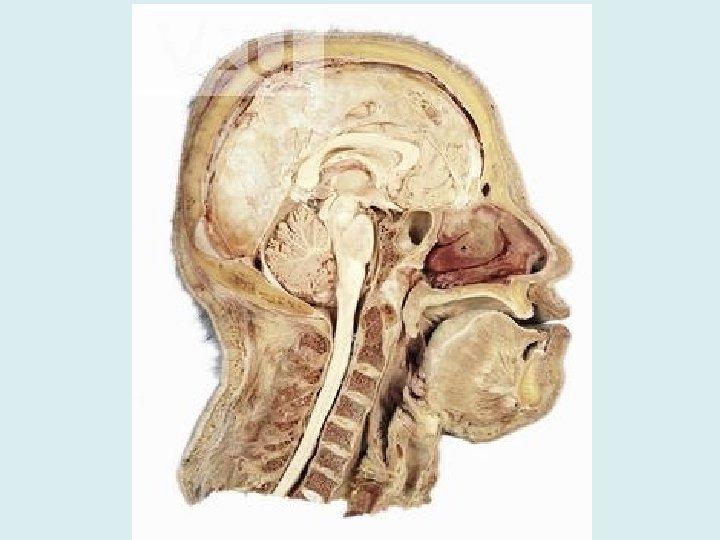

Sections of Brainstem • Midbrain – Conveys ascending and descending impulses • Pons – Conveys ascending and descending impulses – Helps to regulate breathing

Sections of Brainstem • Medulla Oblongata – Conveys ascending and descending impulses – Regulates autonomic activities such as heart rate, blood pressure, breathing, swallowing, vomiting, defecation, sneezing, coughing… the list goes on • As soon as it passes out of the skull (through the foramen magnum), the brainstem is then known as the spinal cord

Central Nervous System • Brain • Spinal Cord – Extends from medulla oblongata (at foramen magnum) to the T 12 vertebrae (last thoracic vertebrae) – Below T 12 is the cauda equina (a collection of spinal nerves)